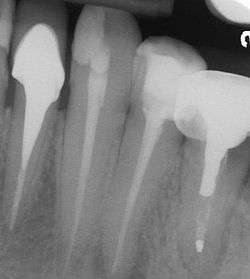

In the picture at right, the two teeth on the extreme left and right are the ones under discussion. The two teeth in the middle have been endodontically treated, but do not have post and cores.